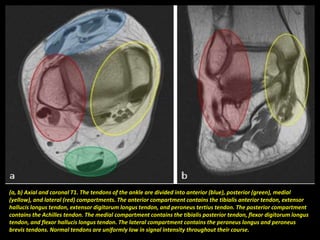

(a, b) Axial and coronal T1. The tendons of the ankle are divided into anterior (blue), posterior (green), medial

(yellow), and lateral (red) compartments. The anterior compartment contains the tibialis anterior tendon, extensor

hallucis longus tendon, extensor digitorum longus tendon, and peroneus tertius tendon. The posterior compartment

contains the Achilles tendon. The medial compartment contains the tibialis posterior tendon, flexor digitorum longus

tendon, and flexor hallucis longus tendon. The lateral compartment contains the peroneus longus and peroneus

brevis tendons. Normal tendons are uniformly low in signal intensity throughout their course.